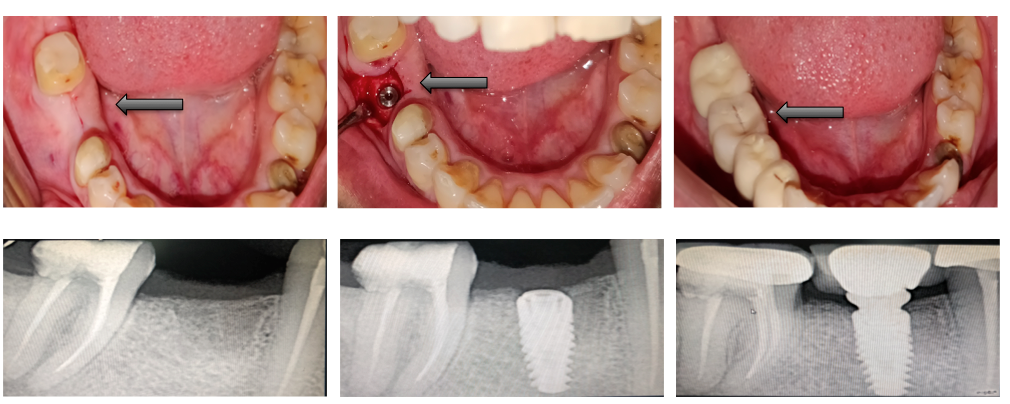

Single Tooth Replacement

Card image